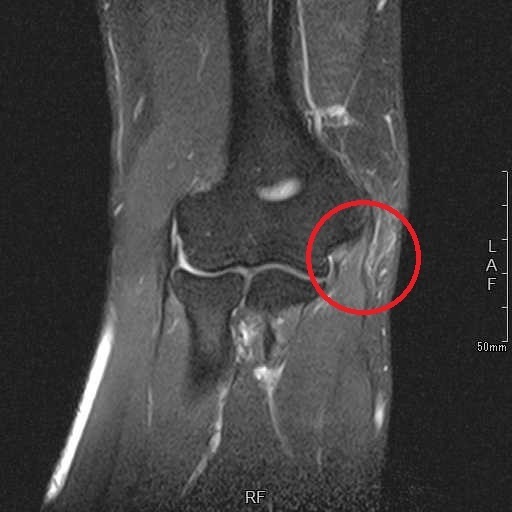

画像検査(MRI):右肘内側の屈筋群起始部の高信号(白い)

MRI画像の変化

| 治療前 1月25日 |

治療後 3月9日 |

体外衝撃波治療によって、1年半以上続いていた痛みは著明に低下し、ゴルフも問題なく行うことができるようになった。その後も症状は再発していない。